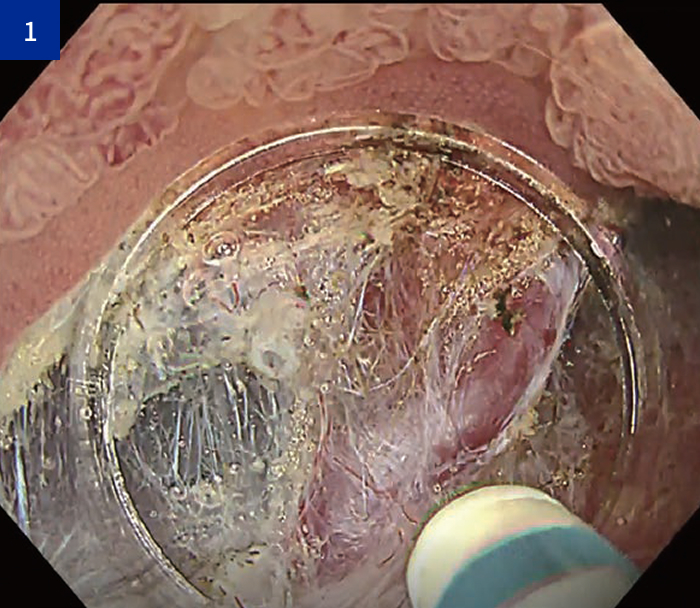

1:切断と凝固のバランス

• ・本症例では、狭いスペースでの剥離操作において、先端ディスクで組織を安定して捉えることで、精密な剥離が可能であった。

・また、出血時にはディスクを収納し、凝固波を用いてゆっくり操作することで、比較的多い出血にも対応可能であった。

• 切断と凝固のバランス